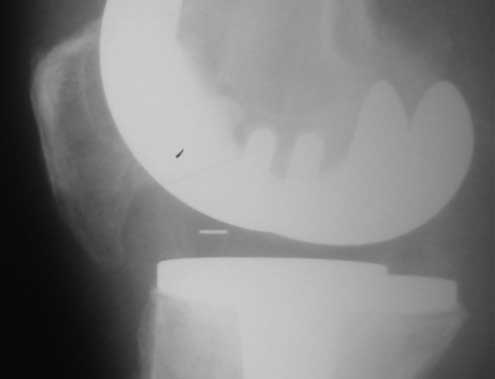

У пациента 50 лет имеется разгибательная контрактура через 8 меспосле ТКА. Уважаемые коллеги. Пациент 8 мес после операции ТКА, в анамнезе – неправильно сросшийся перелом голени, коррекция оси (снимки прилагаются. В настоящее время имеется разгибательная контрактура 10/5/0, на операционном столе было 90/0/5, на момент выписки движения 50/0/0 в надежде на дальнейшую разработку. До эндопротезирования 40/10/0. Глубокая инфекция исключена. Ротация бедренного компонента в норме (по КТ). Вопросы: насколько для такого ограничения критична некорректная установка б/б компонента (я намерял 7 град)? Причина нынешнего состояния, артрофиброз? Какие действия следует предпринять, удаление рубцов, релиз головок 4-главой мышцы? Что-либо другое, ваше мнение? С уважением, Максим Агалаков, Екатеринбург.

а вы уверены, что это артрофиброз, а не patella baja

Рентгеновский снимок хороший, операция выполнена достойно, надколенник не смущает. Остаюсь на своем мнении, артролиз, если смущает давление надколенника при артроскопии помимо артролиза верхнего заворота, боковых каналов и переднего отдела, дополните латеральным релизом надколенника, чтоб уменьшить натяжение.

Низковат, соласен. Соориентируетесь при операции, если ограничивает движения, перенести бугристость или Z-образная тенотомия связки надколенника, артросокпический артролиз обязательно.